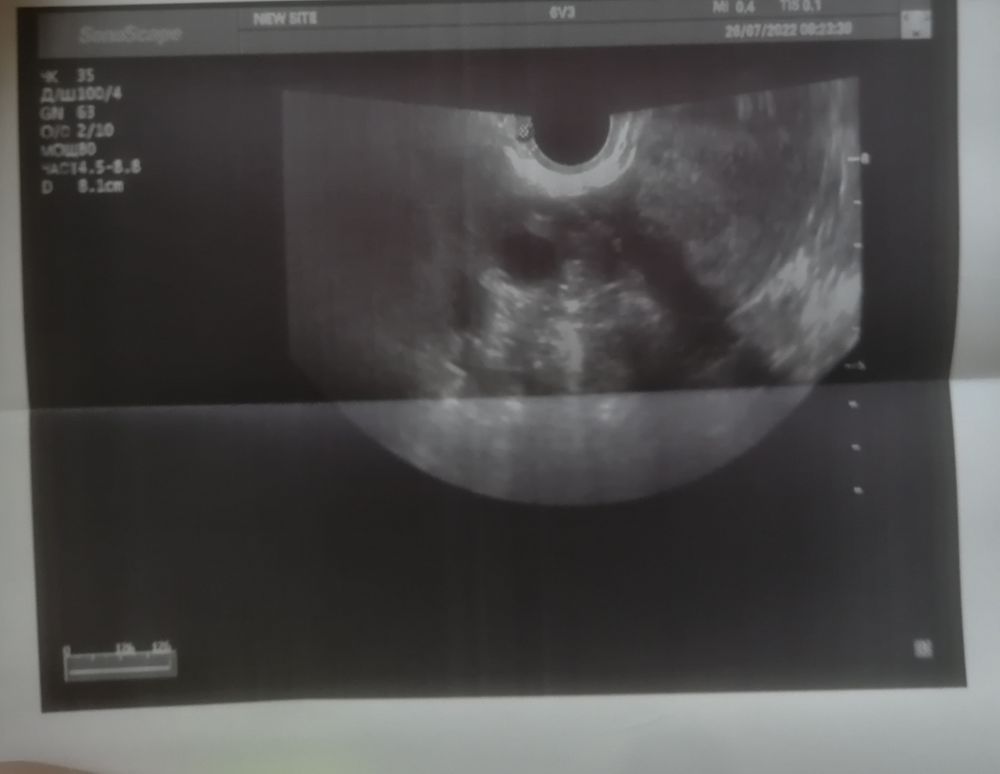

Добрый день девочки. Вообщем ситуация такая, сегодня 20 дц, цикл 28 дней, обычно болит грудь после овуляции всегда, но не в этом месяце, я решила сходить на узи т.к думала что цикл ановуляторный, но узи это не подтвердило и в итоге сказали, что либо

была овуляция двойная и два жёлтых тела, либо одно жт и один дф и овуляция ещё будет. Цикл стабильный, задержек не бывает, максимум 1 день. И как при 28 дневном цикле возможна овуляция на 20 дц, а то и позже, если предположить что это всё таки дф и он 16 мм. Может кто разбирается, что на фото всё таки? Заранее всем спасибо. 🙏